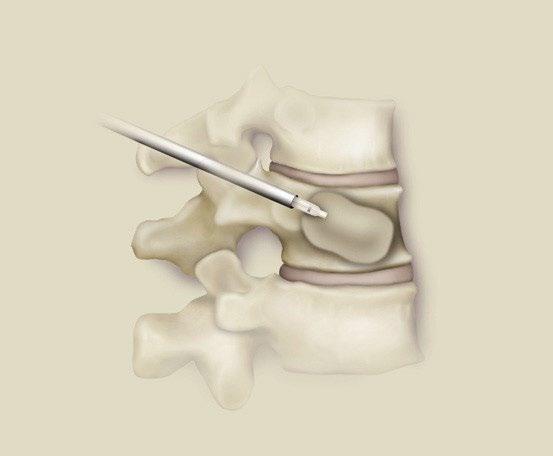

Local Therapy

Kasperk 2012 J Surg Oncol